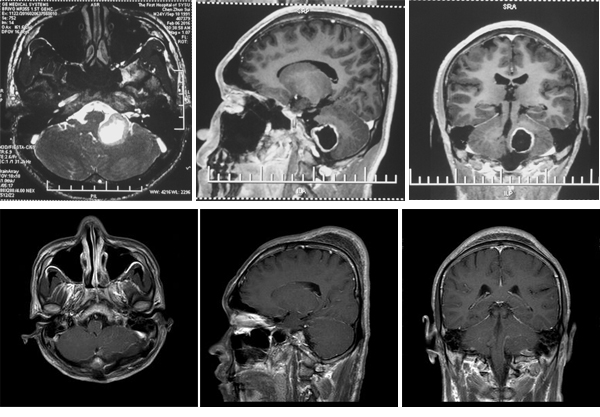

术前与术后影像学检查

陈某近期突然无缘无故的出现头晕,行走不稳,可当时家里人和他都没有在意这些不舒服。可就在近1周头晕加重,且出现左耳听力下降,呕吐,严重影响到了自己的正常生活和工作,这才到广州一家综合医院就诊,行磁共振检查,诊断“左侧桥小脑角区肿瘤”,肿瘤呈囊实性,大小约30mm×22mm×26mm,有蒂长入左侧舌下神经管,增强扫描环形强化,脑干、小脑受压,四脑室稍变窄。这一下就让陈某一家人十分焦急,多方打听后,决定到广东三九脑科医院血管神经外科就诊,办理入院后初步检查显示陈某听力粗测正常右侧正常,左耳听力下降。伸舌居中,耸肩有力。四肢肌力5级,肌张力正常。腱反射正常,巴氏佂阴性。左侧跟膝胫试验阳,步行向左侧偏移。完善CTA以及其他术前检查,积极术前准备,于近期在全麻下行左侧桥小脑角区肿瘤切除术,术中见肿瘤呈淡红色,与迷走神经粘连紧密。小心分离出迷走神经,以及肿瘤脑干面,最后从舌下神经分离出肿瘤,全切肿瘤,术中电生理监测正常,术程顺利,术后给予抗炎,止血,营养神经等治疗。术后病理结果:舌下神经良性肿瘤。

本例患者肿瘤位于脑外桥小脑角池内,位置偏前,属于颅内型,采用乙状窦后入路可更好的暴露肿瘤。因肿瘤体积较大,术中重点注意椎动脉、小脑后下动脉及后组颅神经等的保护。术中应用颅神经和脑干电生理监测,有助于减少术后并发症的产生。